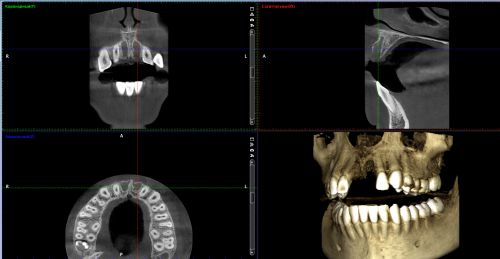

1.Пройти диагностическое обследование - компьютерную томограмму, которая является трехмерным изображением, поэтому позволяет с высокой точностью выявить положение, форму, размеры и строение различных участков верхней и нижней челюсти. Благодаря этому, она является одним из ключевых инструментов современной диагностики в стоматологии.

Фото. Трехмерное изображение челюстей.